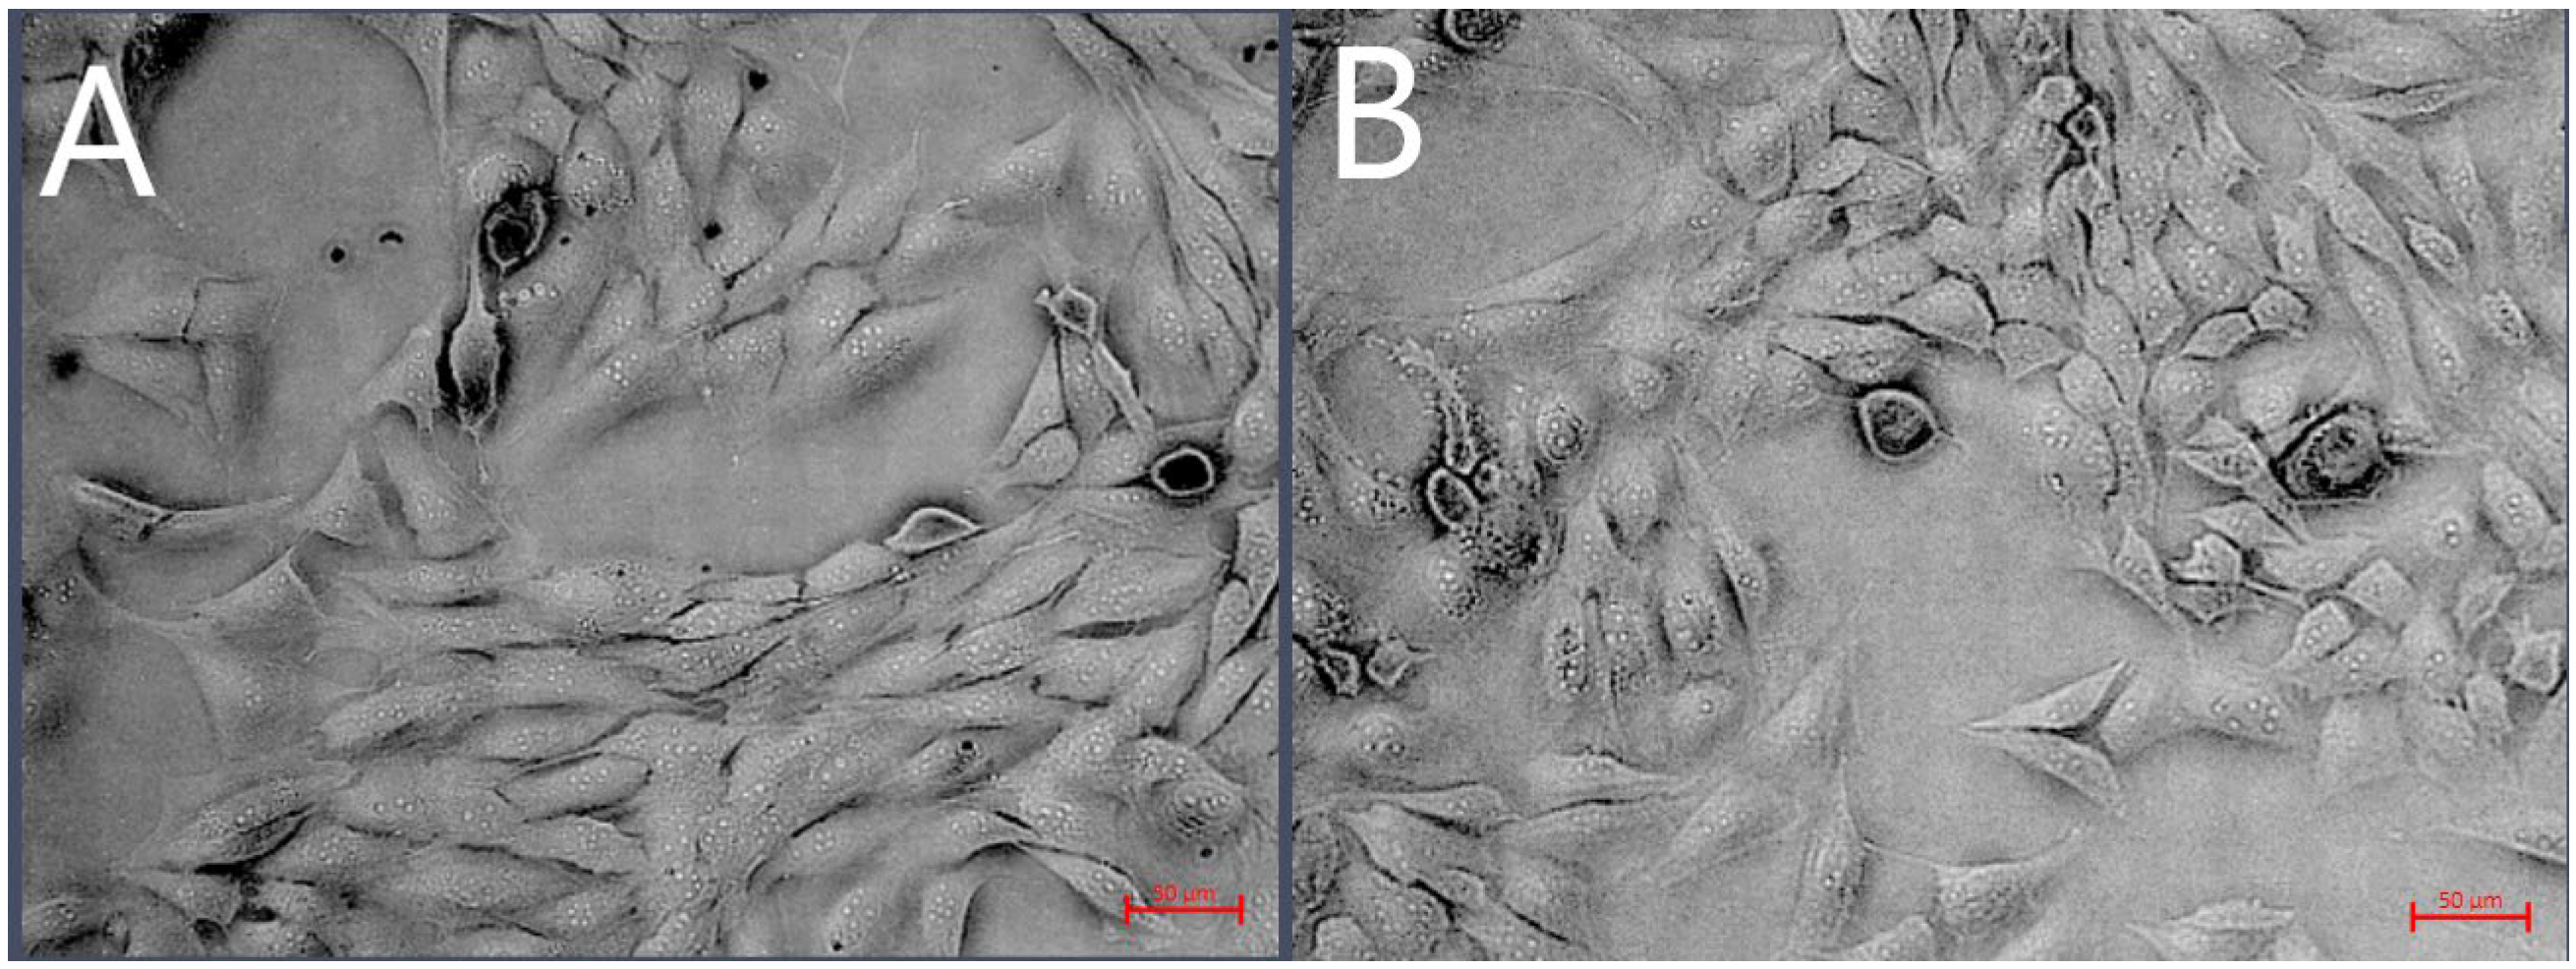

D-17 cells treated with 500 µg/mL (the maximum concentration that does not induce Au-GSH NP aggregation) Au-GSH NPs for 24 h under a contrast-phase microscope did not exhibit any signs of changes in morphology in comparison to the non-treated control cells (Figure 3). Both treated and untreated cells exhibit a similar elongated, spindle-like shape with a comparable density and arrangement. There is no visible evidence of structural damage, cell shrinkage, or detachment. Furthermore, the cell mortality assessed using the Countess II automated cell counter with trypan blue exclusion did not exceed 20% at either tested concentration (200 µg/mL and 500 µg/mL) in D-17 cells. For OSCA-32 and OSCA-8 cells, the same evaluations of morphology and viability were applied in a previous study by our team []. The analyses showed comparable results: no morphological changes or cell mortality below 20%.

Figure 3. Phase-contrast microscopy images of D-17 cells treated with 500 µg/mL Au-GSH NPs (A) vs. non-treated (B) D-17 cells, shown at 20× magnification, scale bar 50 µm.